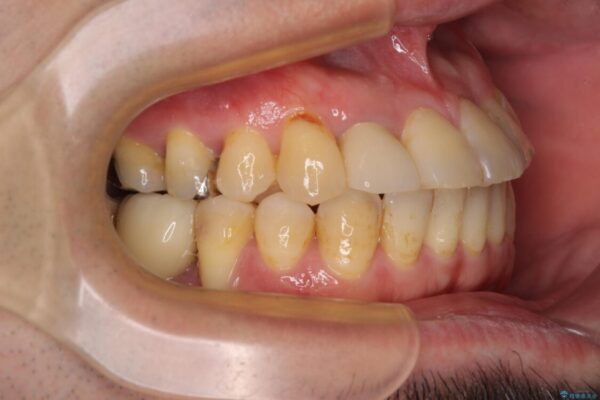

奥歯の痛みと前歯のデコボコを気にして来院された患者様です。

治療計画

左右下顎の大臼歯は、ともに歯根が破折しており、抜歯が必要な状態でした。

放置したことで炎症による骨吸収が顕著であるため、骨造成を併用してインプラント埋入を行うこととしました。

咬み合わせは受け口傾向であり、上顎前歯の叢生が顕著であったことから、第1小臼歯抜歯による矯正治療も検討しましたが、下顎大臼歯を左右ともに抜歯するため、非抜歯による矯正治療を行うこととしました。

治療前

• 割れてしまった奥歯とデコボコの前歯 矯正治療とインプラント治療 治療前画像